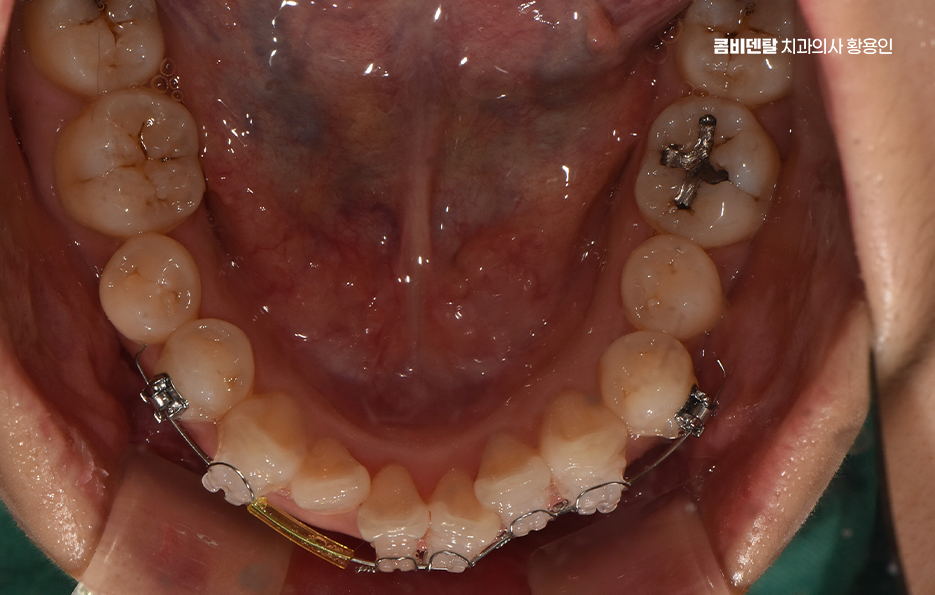

앞니 부분 교정이라는 건 말 그대로 전체 치아를 전반적으로 움직이는 게 아니라, 웃을 때 보이는 앞니 위주로 배열이나 틀어짐, 벌어짐 등을 정리하는 방식으로 앞니 부분 교정은 치료 시간과 비용, 교정 장치에 대한 부담을 줄일 수 있어서 치료가 가능한 케이스에 해당된다면 앞니를 전체교정에 비해 빠르게 개선할 수 있어요

앞니 부분 교정은 단순히 환자분이 원한다고 선택 가능한 것은 아니며 앞니만 따로 움직일 수 있을 만큼 주변 치아나 교합 상태가 안정적인 경우여야만 적용이 가능한 거예요.

앞니 부분 교정 가능한 다음 사례로는 치아가 겹쳐져 있는 경미한 부분 교차 교합인데 특히 아래 앞니 두세 개가 겹쳐 보이거나, 웃을 때 위 앞니 끝이 들쑥날쑥해 보일 때도 앞니 부분 교정으로 배열을 맞출 수 있으며 이런 경우는 부분 교정 만이 아니라 투명교정으로도 가능한 경우도 있어요

그런데 앞니만 건드리는 교정이라 하더라도 치아는 전체적으로 연결돼 있기 때문에, 단순히 눈에 보이는 앞니만 보고 ‘이건 부분 교정으로 되겠지’라고 판단하면 오히려 문제가 생길 수 있어서 앞니 부분 교정도 사전에 정밀한 진단이 필수이고 전체적인 교합 상태, 위아래 치열의 중심선이 맞는지, 앞니의 돌출 각도나 회전 상태, 잇몸뼈의 두께나 여유 공간 등을 모두 고려해서 가능 여부를 판단해야 하는 거예요

부분교정이 가능하다고 결론이 나면, 그때부터 어떤 방식으로, 얼마나 오랜 시간 동안 치료할 수 있을지 구체적인 계획을 세우게 되는 것이고 여기서 중요한 건, 부분 교정이라고 해서 모든 케이스가 간단하게 끝나는 건 아닌데 보통 3개월에서 6개월 정도면 끝난다고 하지만, 케이스에 따라 8개월 이상 걸리는 경우도 있고 유지 장치 착용도 고려하면 그저 단기 치료로만 끝나는 것은 아니기 때문에 치료 전에 교정 전문의와 충분히 먼저 상의가 필요한 거예요